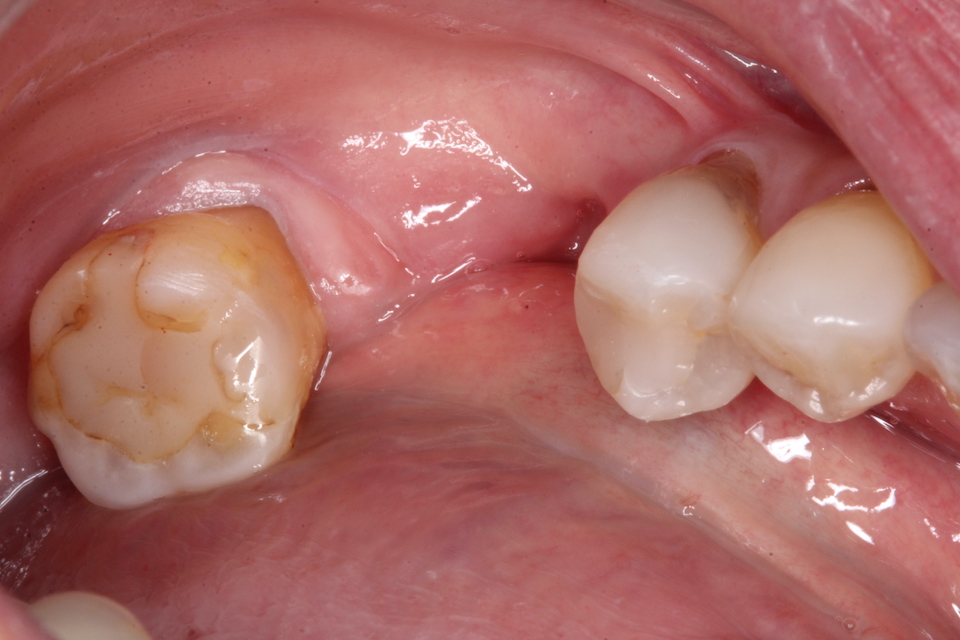

究極のワンオペ歯科治療シリーズ1.0

最近、歯科業界も少子高齢化で助手も歯科衛生士も不足気味、それに加えて不況で助手を雇うお金もないのか、人手不足と経費削減の為ワンオペ歯科治療をしよう!というセミナーまであるらしい。僕も歯科技工は外注せずになるべく口腔内で終わるべくワンオペでやっているので、それをシリーズ化してみようと思う。50代女性、左上6欠損この方なるべく削りたくないということで8年前、接着性義歯を作った。接着性の義歯というのは取り外しの義歯をスーパーボンドで接着するというもので、普通はないものです。これもワンオペ向きの治療法で歯科技工も口腔内での治療も難しくなく時間もかからない、患者にとってもメリットが大きいのでご紹介してみます。その時の画像2017/07/12奥の7番はハイブリッドCK、手前の5番はCRで再建している。ほとんど削っていない。金属は銀合金を使っている。酸化皮膜があるのでスーパーボンドの接着性が良い。強度もまあまあだ。何より柔らかいので研磨作業が楽だ。青のシリコンポイントだけで研磨できる。金属も安いし、これはワンオペにはありがたい。口腔内セット次回は8年後、つづく